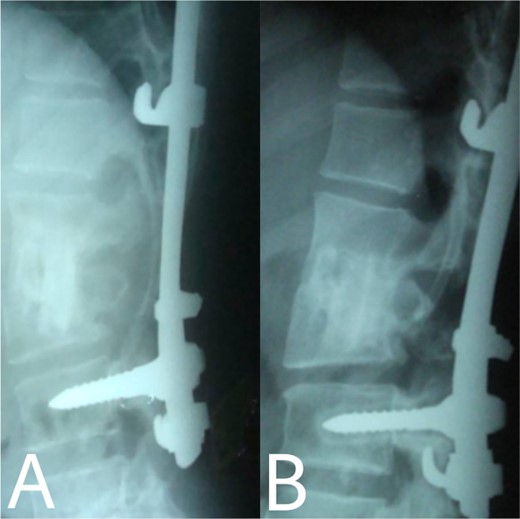

(A, B) 2, 4 months after single-stage posterior extensive debridement and fibular autograft implantation followed by supplemental posterior instrumentation performed to treat the spinal infection.